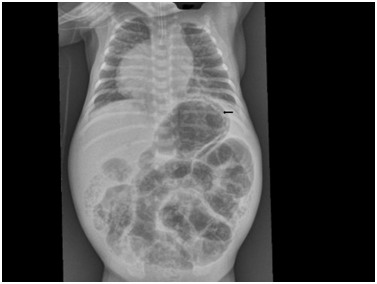

A male infant, twin B was born at 32weeks’ gestation by cesarean section due to fetal distress to a 26year old gravida 2 and Para 1 mother. The antenatal ultrasound of our patient showed congenital heart disease. The maternal history was insignificant. He weighed 1880grams and had Apgar scores of 9 and 9 at 1 and 5minutes respectively. He developed respiratory distress immediately after birth and required intubation and mechanical ventilation. There was no dysmorphic features. Echocardiogram and C.T cardiac with contrast showed dextrocardia, trunk’s arteriosus, interrupted aortic arch, large ventricular septal defect and patent ductus arteriosus. He was clinical stable and was started on enteral feeds. He had episode of gastric aspirates but they were considered insignificant. At two weeks of age he became septic with abdominal distension. He required dobutamin to restore his low blood pressure. Abdominal radiographs showed gastric and intestinal pneumatosis without any evidence of free intraperitoneal or portal venous air (Figure 1). Leukopenia and thrombocytopenia were present. He was started on antibiotics (ampicillin, gentamicin and metronidazole). He passed bloody stools with mucous. He required several platelet transfusions to correct the severe thrombocytopenia. The septic workup showed sterile blood cultures. His abdominal radiographs improved on day five of treatment (Figure 2). His head ultrasound was normal. The clinical condition of the infant significantly improved.

Figure 1 Abdominal X-ray of our patient showing gastric and intestinal pneumatosis.